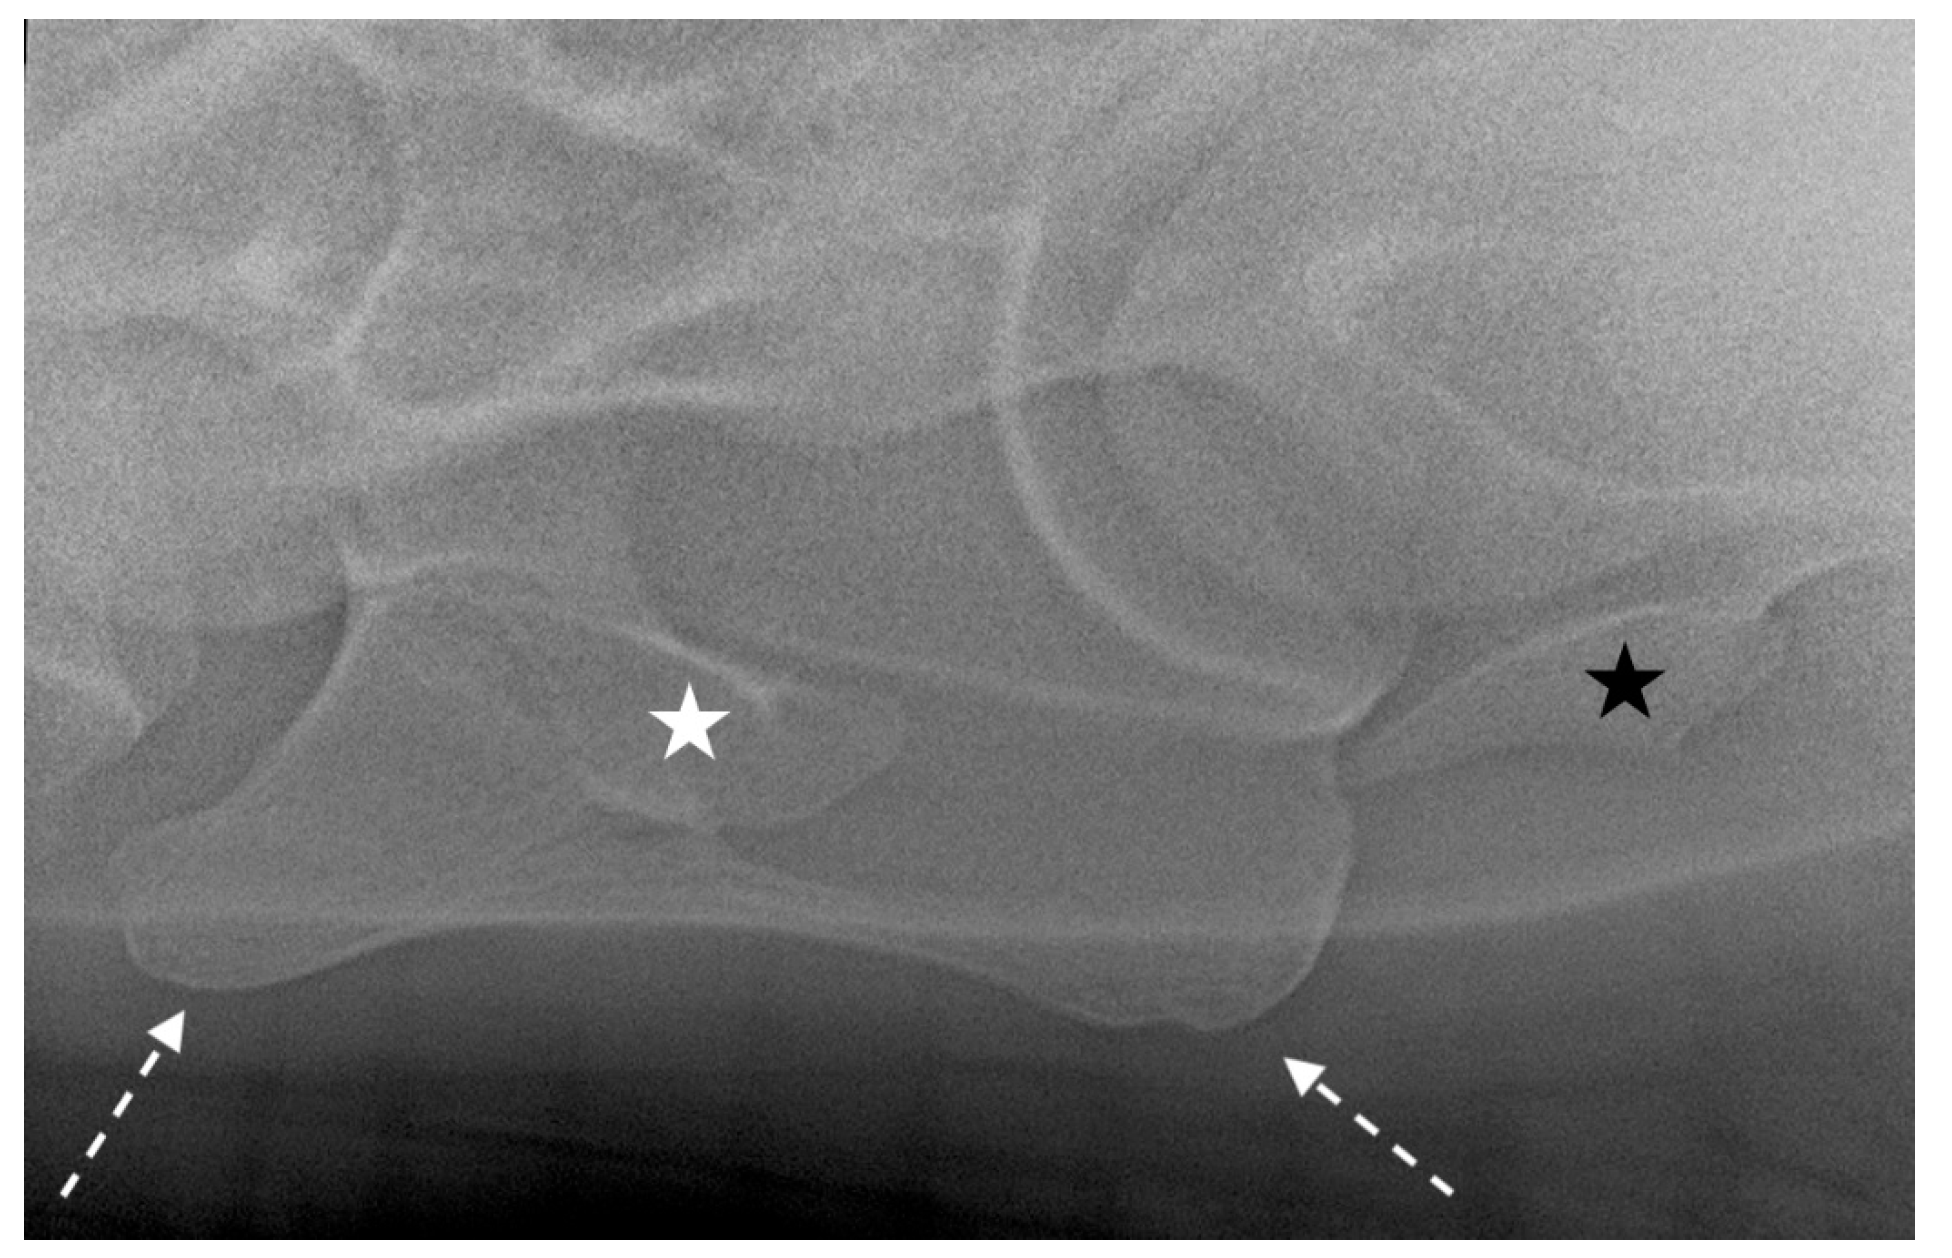

2.3. Radiographic Method

2.4. Classification System